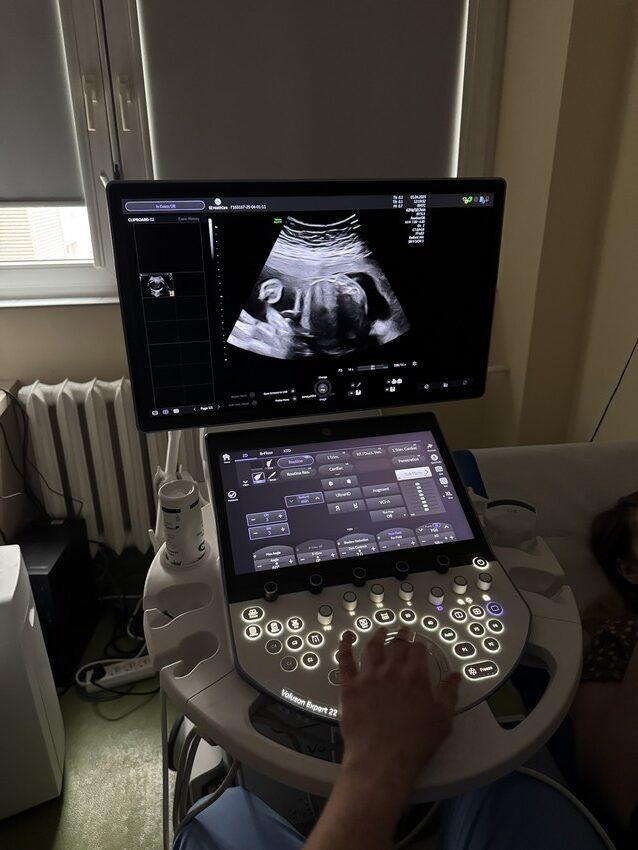

To absolutna nowość w rzeszowskim szpitalu. Od kwietnia Poradnia Położniczo-Ginekologiczna Klinicznego Szpitala Wojewódzkiego w Rzeszowie realizuje Program Badań Prenatalnych, finansowany przez NFZ.

Badania prenatalne umożliwiają wczesne wykrycie ewentualnych wad rozwojowych u dziecka. W niektórych przypadkach pozwalają na leczenie jeszcze w trakcie ciąży. Dają też rodzicom czas na przygotowanie się do specjalistycznej opieki po narodzinach.

- I trymestr (11.-14. tydzień ciąży) – badanie USG oraz testy biochemiczne (PAPP-A i β-hCG).

- II trymestr(18.-22. tydzień ciąży) – szczegółowe badanie USG oceniające rozwój dziecka.